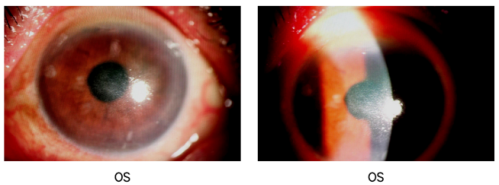

查体:视力FC/40cm(OS)

图片

IVCM:左眼角膜上皮大部分缺失,神经纤维未见,未见炎性细胞浸润。浅基质细胞活化肿胀,深基质细胞形态可。内皮细胞模糊不清,伴高反光物质浸润。

诊断:左眼病毒性角膜内皮炎,双眼人工晶状体植入状态

治疗:左眼AMT+激素+抗病毒+人工泪液

2月后复查:视力0.5(OS)